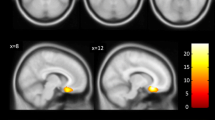

GAT haplotype influence on amygdala volume

Considering the effects of the risk haplotype, repeated measures ANCOVA for relative amygdala volumes revealed a significant effect for factor DGKH GAT haplotype (F = 4.6, df = 1, 57, p = 0.035, effect size partial η 2 = 0.08). A main effect for hemisphere was observed (F = 50.4, df = 1, 57, p < 0.0005, volume right >left). Following separate analysis for right and left side showed significant effects of diagnosis for the left amygdala (F = 7.2, df = 2, 57, p = 0.002, highest volume in controls and lowest in schizophrenic patients). There was no significant interaction between sex and genotype on amygdala volume. There were no significant effects of the DGKH genotype on the left amygdala volume (F = 1.8, df = 1, 57, p = 0.19). For more details, see Fig. 1. Regarding the right amygdala, there were significant effects of the DGKH haplotype on volume (F = 6.3, df = 1, 57, p = 0.015, partial η 2 = 0.10), in that risk haplotype carriers had increased volumes. For details, see Fig. 2.

Relative left amygdala volume for bipolar disorder (BD), schizophrenia (SCZ), and healthy controls (CTRL). ALL includes BD and SCZ without CTRL. The graph displays mean values and standard deviations. GAT haplotype carriers in the BD group had a significantly greater amygdala volume (adjusted for total brain volume) compared to subjects carrying no GAT haplotype. *p < 0.05

Relative right amygdala volume for bipolar disorder (BD), schizophrenia (SCZ), and healthy controls (CTRL). The graph displays mean values and standard deviations. GAT haplotype carriers in the CTRL group, BD, and SCZ as one group (ALL) had a significantly greater amygdala volume (adjusted for total brain volume), compared to subjects carrying no GAT haplotype. *p < 0.05

A sub-analysis on BD and schizophrenia alone compared to healthy controls (ANOVA, between-subject factors DGKH, sex; inner-subject factor hemisphere, covariate age/disease duration; followed by side-separated analysis) revealed an association of the DGKH GAT haplotype with increased amygdala volume in the bipolar patients (F = 4.3, df = 1, 24, p < 0.05, partial η 2 = 0.15), but not in schizophrenia patients and controls (Figs. 1, 2). Additionally, there were significant sex (F = 11.0, df = 1, 24, p = 0.004) and hemisphere effects (F = 35.8, df = 1, 24, p < 0.0005) in bipolar patients. The relative volume of the right amygdala was larger than on the left side and females had an increased volume as compared to males. Subsequent univariate analysis showed significant effects of DGKH genotype on left amygdala (F = 7.8, df = 1, 24, p = 0.010, partial η 2 = 0.24) and also significant sex effects (left: F = 7.3, df = 1, 24, p = 0.013, right: F = 9.2, df = 1, 24, p = 0.006). These data did not change when lithium effects were controlled for.